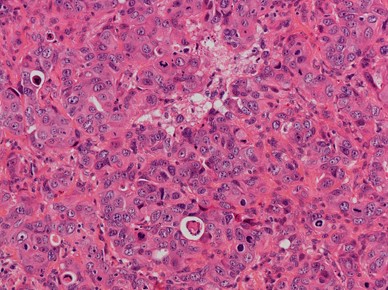

Intestinal-type adenocarcinoma, solid subtype. The tumor displays a diffuse growth pattern with minor amounts of poorly differentiated glandular lumina. There is high mitotic activity. H–E stain ×250

Fig. 4

figure 4

Intestinal-type adenocarcinoma, mucinous subtype. a Tumor cells form clusters with glandular lumina, b and strips with goblet-type cells, and are surrounded by ample pools of mucin. H–E stain ×400